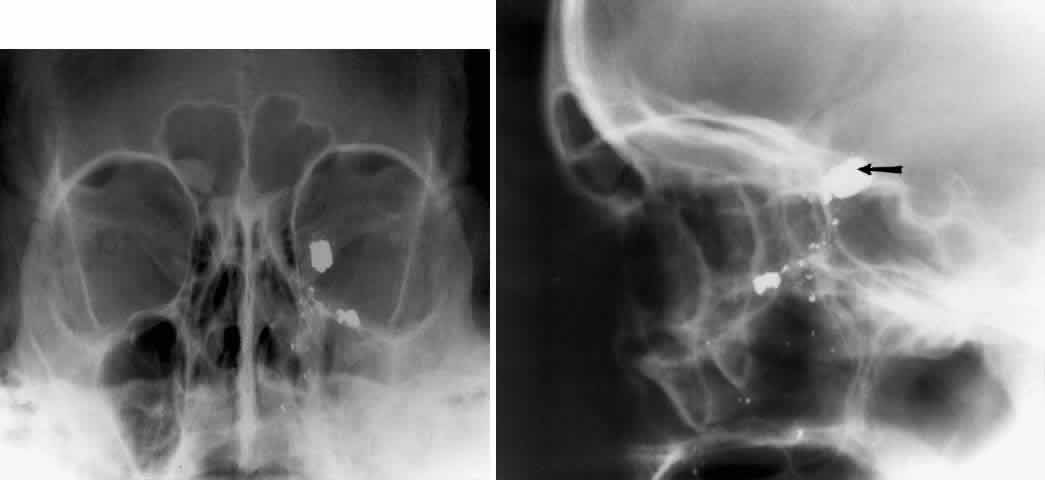

The posterior segment of the lateral wall courses posterior medially and can be seen in anterior projections such as the Caldwell view. This view allows direct visualization of the greater sphenoid wing contribution to the lateral wall. Bone density changes in the greater wing of the sphenoid, such as from a meningioma, can be detected. Fractures of the lateral orbital wall can occur from blunt trauma to the malar prominence. The zygomatic complex fracture (tripod) results from separation of the zygomatic-frontal, zygomatic-temporal, and the zygomatic-maxillary sutures. These fractures are associated with an inferior displacement of the malar prominence and a rounded lateral canthus (Figs. 8 and 9).

Fig. 8. A zygomatic complex fracture (tripod) after blunt trauma to the right cheek. Note the right zygoma is inferiorly displaced. (a, zygomatic-frontal suture separation; b, orbital rim disruption; c, opacification of maxillary sinus)

Fig. 9. Bilateral zygomatic complex and LeFort II fracture after reduction using fixation plates. Caldwell projection shows good alignment of orbital margin and zygomatic bones.